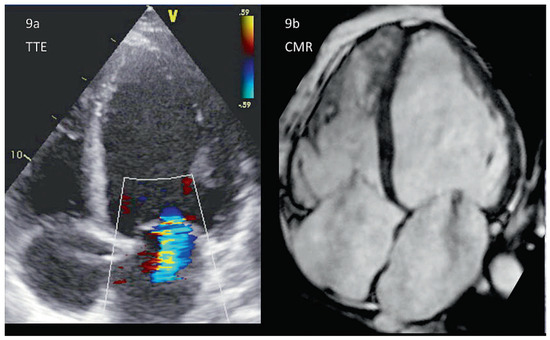

In current clinical practice, choosing the optimal imaging technique for the quantification and differential diagnosis of mitral valve insufficiency constitutes a challenge, even for...